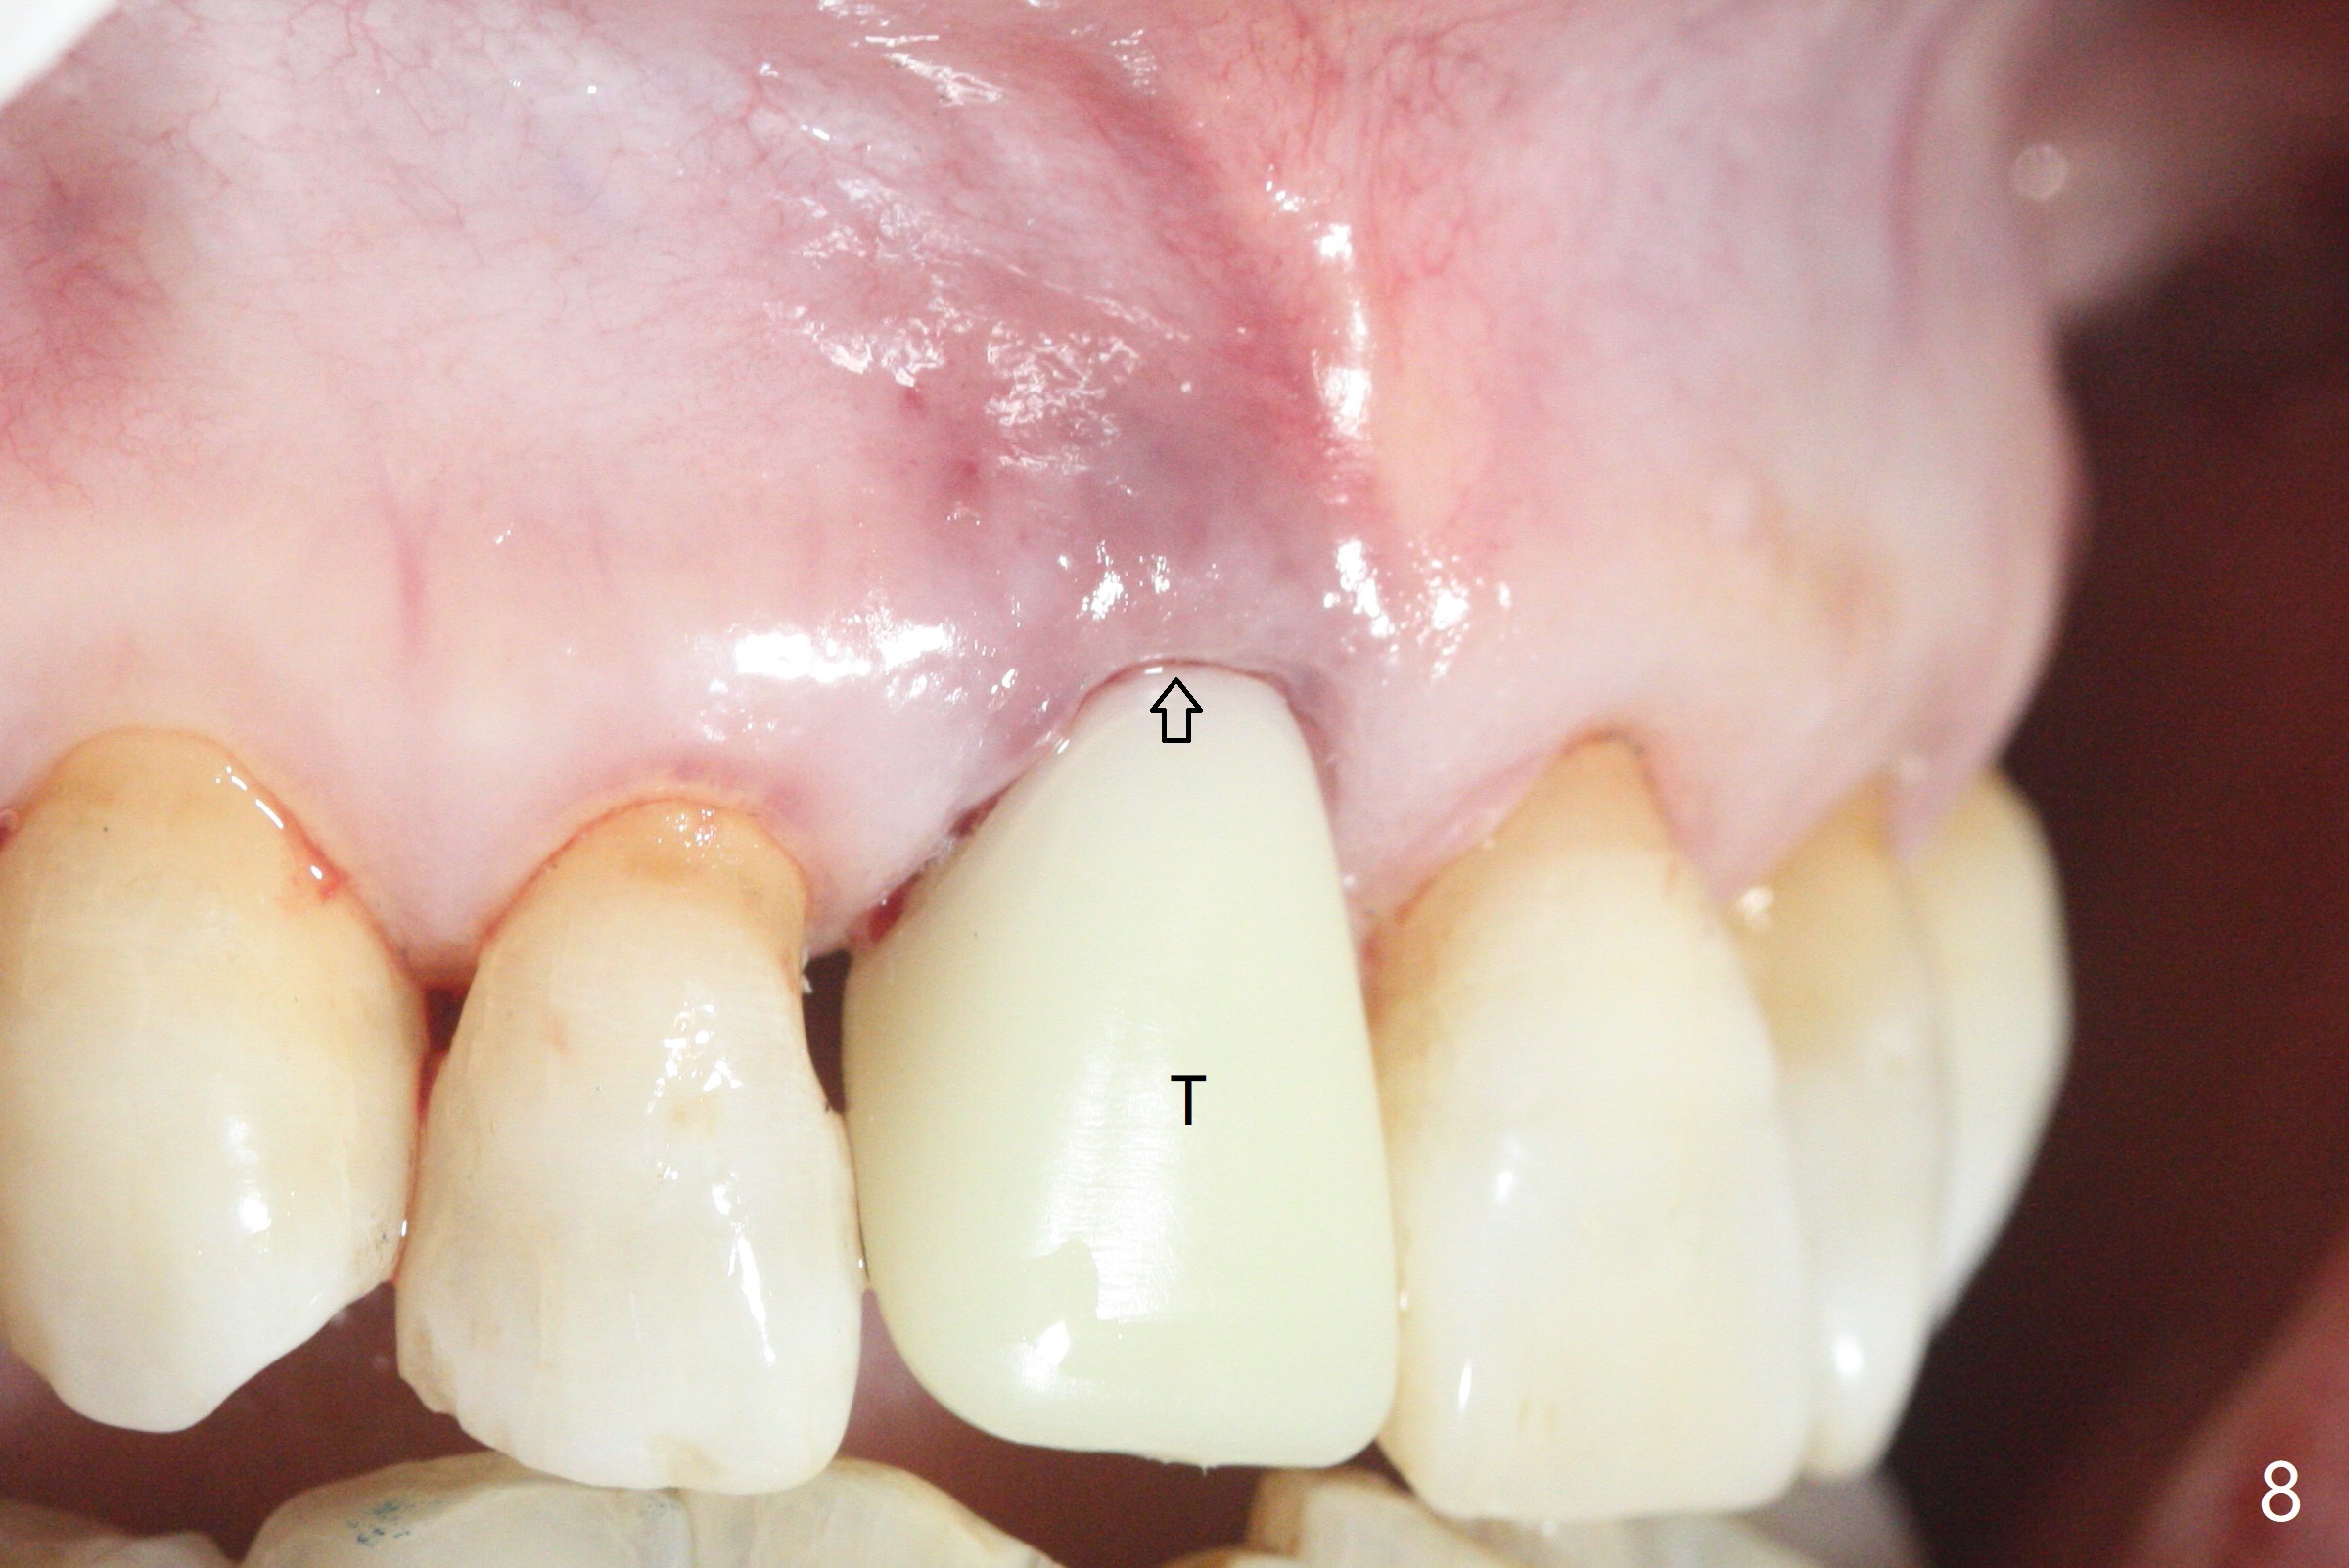

59岁女术前右下1,2切缘磨短后,右上1颊侧移位得到纠正(图一(咬合创伤))。拔牙后证实颊侧骨板缺失,钻洞始于腭侧(图二),当1.5毫米钻头感觉刚穿破鼻底时,置入2.5x14(4)毫米一段式植体,好像进入鼻腔,但是扭力<10Ncm(图三)。把一张PRF膜放入牙槽窝,一端紧贴颊侧牙龈腭侧,另一端放置颊侧牙龈颊侧(图四),然后开始用粘性骨粉(图五,七:*(100%皮质骨))充填颊侧间隙。后者填满时(图五:*),将外面一端PRF翻转覆盖牙槽窝开口,并插入基台固定(图六),最后插入龈下,用临时牙冠固定(图八(T),九(*:PRF))。术后九天牙龈退缩(图十:^),临时牙冠突出(*),后者龈缘和切缘进行调整,缩短(图十一,十二),少许骨粉暴露(图十二:>),十四天后牙龈往下生长,好像形成角化龈(图十三:*)。